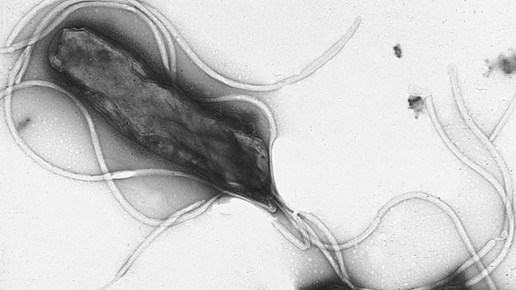

H. pylori ist ein gramnegatives Stäbchenbakterium und kann – im Gegensatz zu den meisten anderen Bakterien – das saure Milieu im menschlichen Magen überleben, obwohl es säureempfindlich ist. Dazu hat hat der Keim Anpassungsmechanismen ausgebildet, die ihm das ermöglichen: Als Überlebensstrategie bildet der Erreger Urease, die die Umwandlung von Harnstoff in Ammoniak katalysiert. Letzteres hebt den pH-Wert der Umgebung an, ein neutrales Milieu entsteht. Diese Reaktion wird auch diagnostisch ausgenutzt (Helicobacter-Urease-Test). So kann sich H. pylori in und unter die Magenschleimhautbarriere einnisten. Seine Geißeln (Flagellen) sind mit einer säurestabilen Hülle überzogen. So kann sich das Bakterium im zähen Magenschleim bewegen und an der obersten Schleimhautschicht festhalten.